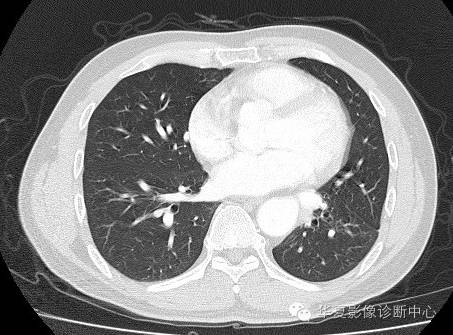

| 影像表现及分析: | 影像表现:定位左下叶;左下叶体积缩小,整体密度增高,支气管分布正常,其内见血管增多,但是走形正常,未见杂乱、迂曲的血管影;血管连向肺门下方软组织密度结节灶,结节与主动脉分界不清,增强后,见降主动脉发出异常粗大血管供血整个左下叶,左下肺动脉细小。 |

异常体动脉供应正常下肺基底段完整含义为起源于降主动脉的异常动脉供应下肺基底段,而基底段支气管树和肺实质正常,同时基底段肺动脉缺如或狭窄【大部分缺如(完全型),部分狭窄(不完全型)】;95%以上累及左下肺,因此也称为异常体动脉供应正常左下肺基底段。 病因尚未明确,可能是胚胎发育时期供应肺芽的背主动脉原始小分支退化不全,与肺实质形成异常连接,并影响肺动脉与肺血管床连接而导致此部位肺动脉发育不良,而支气管、肺组织的发育未受影响。本病的病理生理基础为左向左的分流,体动脉供应的肺组织充血,体循环的高压可增加肺血管床的压力和左心负荷,同时也增加肺循环量和压力而增加右心负荷,导致各种临床症群。本病可无临床症状,部分患者可有咯血、呼吸道感染、呼吸困难、充血性心力衰竭。 影像表现:左肺下叶体积缩小,整体密度稍增高,支气管树走形、分布正常,血管增多、稍增粗;增强后显示左下肺动脉幼小,甚至不发育;下叶由主动脉发出的粗大血管供血。 |